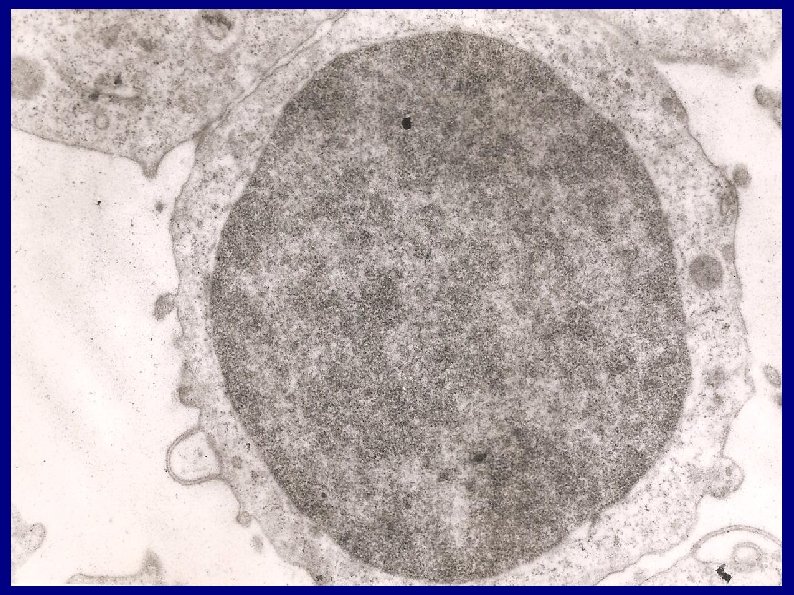

* Otro hallazgo fue que existe en pacientes chagásicos agudos y crónicos una numerosa población de linfocitos que muestran producción de substancia PAS positiva , concentrada en numerosas áreas de reacción de color rojo magenta, en sus citoplasmas, que se observa como 30 ó 40 gránulos. Ese estudio fue extendido a una casuística numerosa, que mostro la constancia de dicha característica. (Cabral HRA, Lancet , 1: 1356 -1357, 1971)

Fotomicrografías de linfocitos PAS positivos

Demostración mediante roseta E de la naturaleza de célula T de linfocito PAS positivo

Linfocitos PAS positivos

La investigación de gránulos PAS positivos en linfocitos fue propuesta como un método de diagnóstico de Chagas el cual tuvo coincidencias , con el resultado positivo de pruebas serológicas para esa afección.

Buscamos y obtuvimos muestras cardíacas de corazones de pacientes chagásicos fallecidos por su cardiopatía (en este trabajo tuve la colaboración de la Dra M. Glocker quien fue patóloga residente en el Hospital San Roque de Córdoba , donde se obtuvo las muestras) Así, comenzamos a investigar la presencia de linfocitos PAS positivos en dichas muestras. Se los hallo predominando en los infiltrados celulares , y adheridos a fibras miocárdicas que mostraban signos de daños , por lo cual se infirió que tienen un rol en la producción inmunopatológica de lesiones cardíacas chagásicas.

La substancia PAS positiva de los linfocitos de chagásicos corresponde a Interferon gamma: Es importante que logramos determinar recientemente que la substancia PAS positiva de los linfocitos de chagásicos corresponde a Interferon Gamma , lo cual, aumenta los datos para su rol inmunopatogénico en esa cardiopatía.

Estudios sobre linfocitos PAS+ Nuestros estudios sobre la naturaleza de la substancia PAS positiva de los linfocitos de chagásicos fueron realizados mediante inmunohistoquímica mediante anticuerpos monoclonales , desde la hipótesis que propusimos de que se trataría de IFN -gamma (basados en que junto a los linfocitos PAS positivos hallamos importante infiltración de macrófagos).

Nuestra idea fue que podía tratarse de la substancia linfocitaria antiguamente llamada factor de inhibición de la migración de macrófagos (MIF) Tuvimos en cuenta que el MIF se trataba de una glucoproteína: El antiguo MIF corresponde hoy a Interferón gamma (lo cuales son glucoproteínas).

Inmunopatología en Chagas Según trabajos nuestros, en Chagas, los tejidos están infiltrados predominantemente por linfocitos. Además, estas células muestran evidencias de ser productores- secretores de substancias PAS positivas, que son glicoproteínas y reaccionan con anticuerpos monoclonales antiinterferongamma. Son, al mismo tiempo, células T CD 4 positivas y son también CD 45 RO positivos. (Resultados obtenidos mediante anticuerpos monoclonales e inmunohistoquímica. ) Esas células son más del 75% de las células intracardíacas infiltradas.